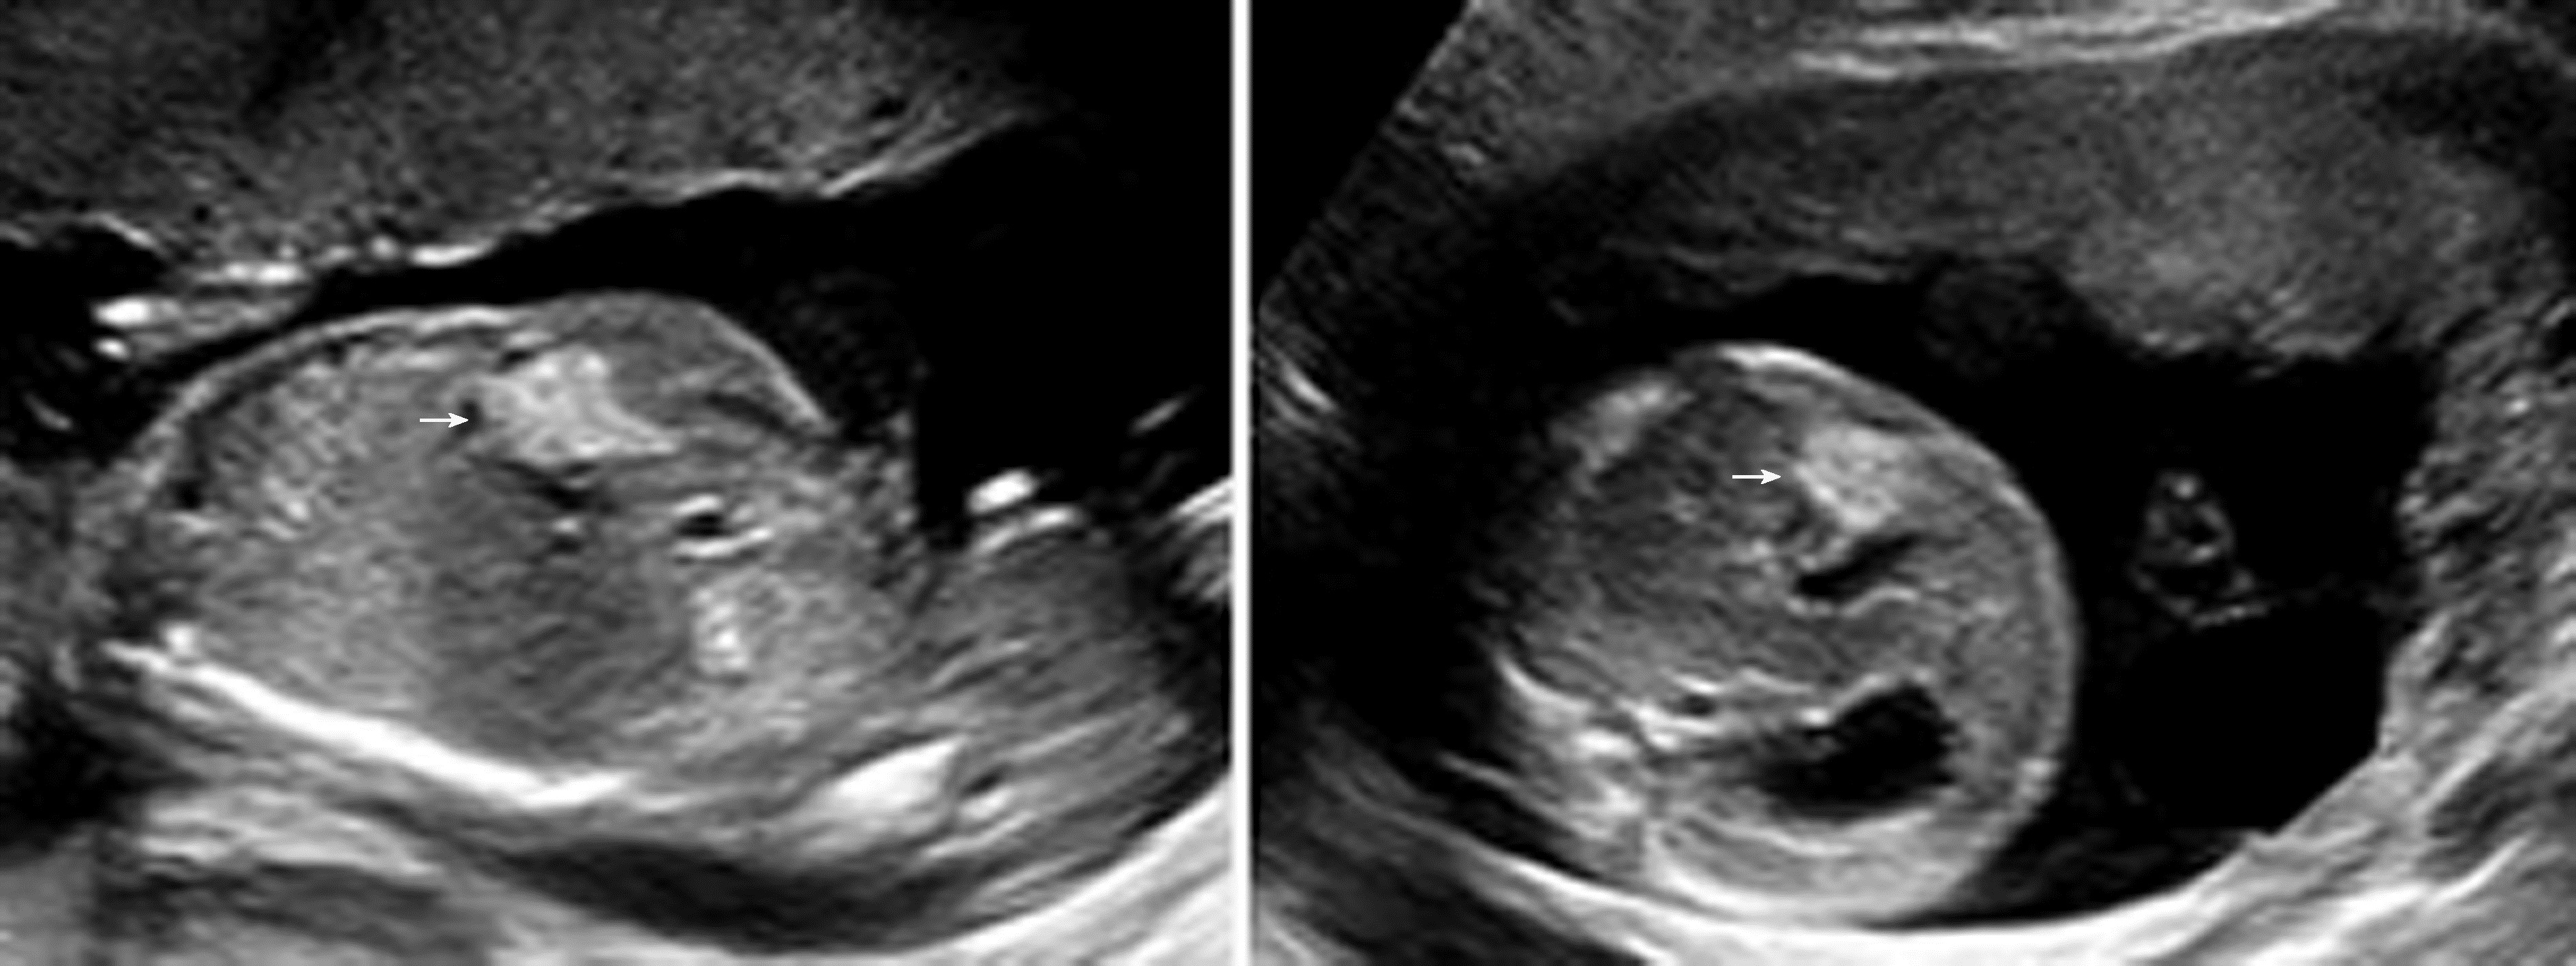

肝脏肿瘤少见,产前超声表现为肝内单个或多个低或高回声团块,部分可有钙化。文献报道的胎儿肝脏肿瘤有肝囊肿、肝血管瘤、肝母细胞瘤、肝腺瘤、错构瘤、肝转移性肿瘤等(图2)。较大的胎儿肝血管瘤及肝母细胞瘤,可导致肝脏增大,多为混合性回声肿块。较大的胎儿肝血管瘤可出现广泛的动静脉瘘而导致胎儿高心输出量性心力衰竭,进一步发展可导致胎儿水肿,但这种情况相当罕见。诊断先天性肝囊肿时,应注意与胎儿胆囊、胎儿肝内段脐静脉曲张等相鉴别。肝肿瘤较大伴胎儿水肿者,预后不良。肝母细胞瘤及转移性肝肿瘤预后不良。单纯肝囊肿预后良好,但合并胎儿多囊肾者预后不良。

图2 孕29周胎儿肝脏血管瘤